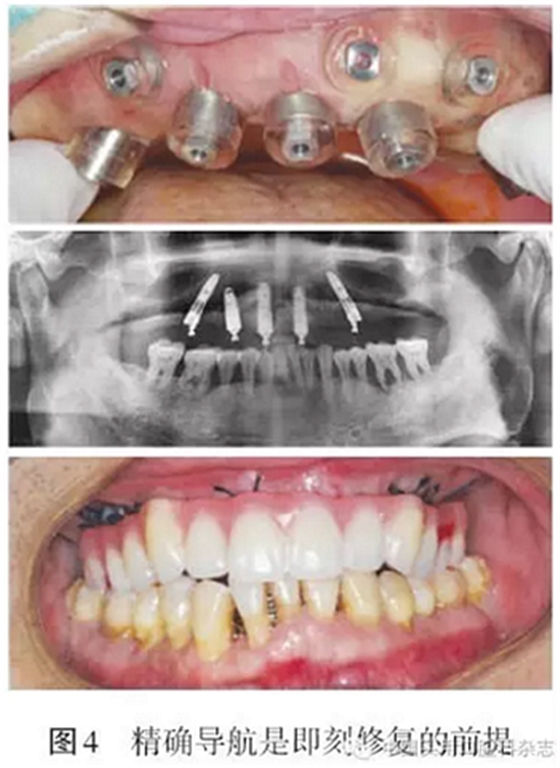

同全口種植固定義齒修復(fù)設(shè)計流程大致相同,但All-on-4術(shù)式多采用即刻修復(fù)即刻負重。因此在制作放射性導(dǎo)板時,應(yīng)同時制作過渡性義齒。在種植設(shè)計過程中,應(yīng)利用傾斜種植體最大限度的延展近遠中向長度,減少游離端懸臂的長度。在設(shè)計后牙區(qū)傾斜種植體時,要充分考慮上頜竇前壁、頦孔等重要解剖結(jié)構(gòu),同時要注意合適的角度基臺的選擇,保證即刻修復(fù)能夠?qū)崿F(xiàn)(圖3~4)。